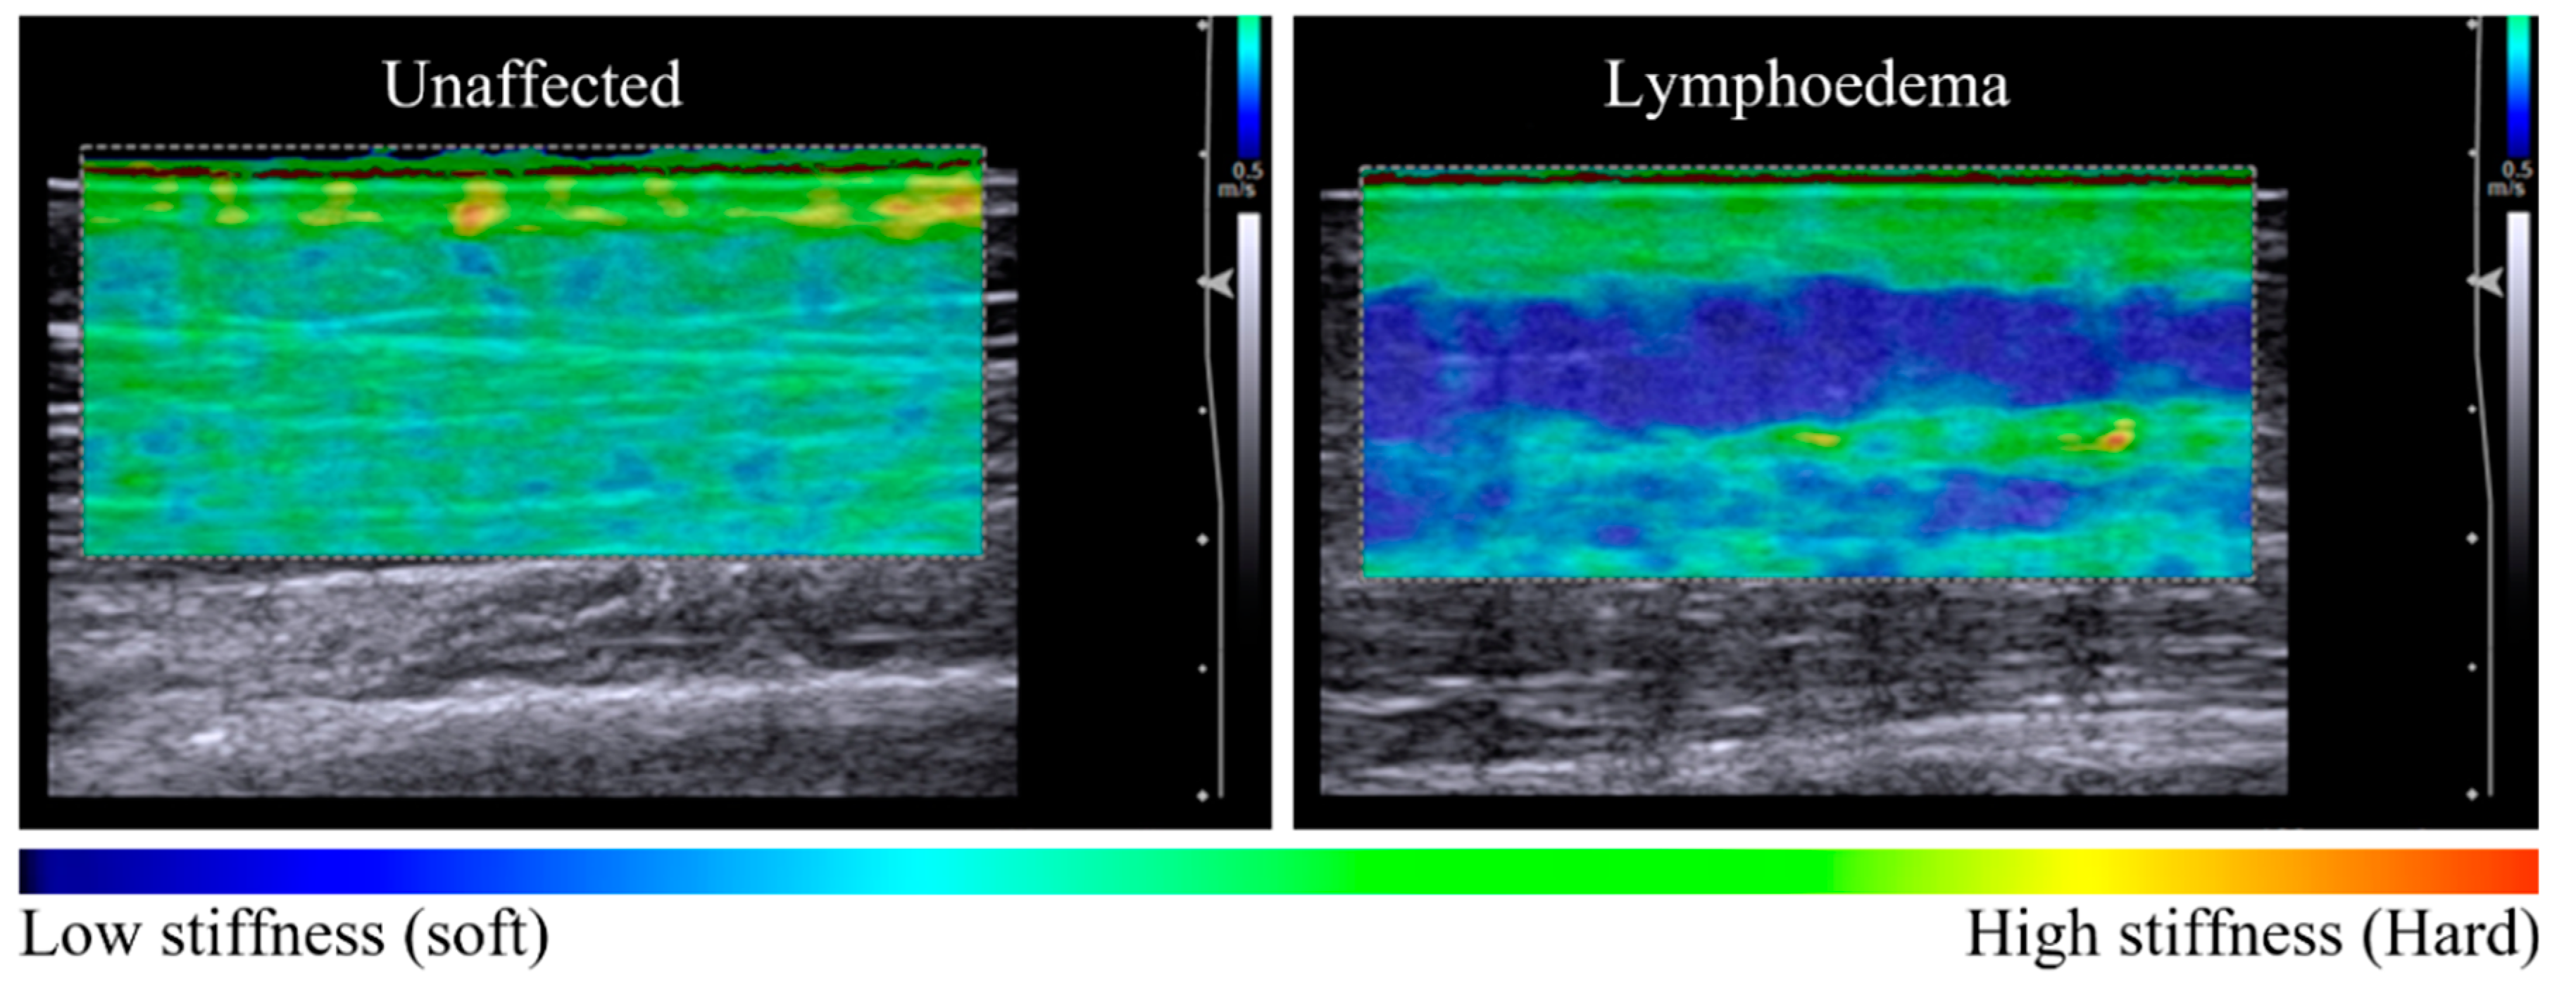

Imaging indicated that lymphoedema alters the distribution of tissue stiffness across dermal and subcutaneous layers. Unaffected tissue was observed to have a relatively homogenous distribution of tissue stiffness across tissue layers in elastography maps and coincided with a low dermal:subcutaneous stiffness ratio. Lymphoedema-affected tissue exhibited higher stiffness ratio values compared to unaffected sites (p = 0.005), corresponding with discernibly heterogenous elastography maps (Table 2) (Figure 1).

Figure 1.

Elastography maps indicative of tissue stiffness distribution observed between unaffected and lymphoedema-affected tissue (posterior forearm, participant 11). The unaffected tissue is relatively homogenous in colour across the dermal and subcutaneous layers, with a tissue stiffness ratio of 1.38 (left panel). There is a difference in tissue stiffness between tissue layers of the lymphoedema-affected site with a tissue stiffness ratio of 2.69 (right panel). The subgroup analysis of seven sites compared elastographic imaging before and after a 60-s pitting test. In Figure 2, pre-test images for each series are similar, with a heterogenous elastographic map showing lymphoedema-affected dermal stiffness greater than subcutaneous stiffness.

Our results show dermal stiffness was consistently greater than subcutaneous stiffness regardless of whether the tissues were lymphoedematous or not. The difference in elastography stiffness values were representative of differences in tissue layer structure and density. Furthermore, healthy unaffected tissue exhibited integration of dermal and subcutaneous tissues, which manifested as a well-integrated distribution of tissue stiffness between layers. Unaffected tissue was observed to have a propensity toward homogenous elastographic maps with lower dermal:subcutaneous stiffness ratios relative to contralateral matched lymphoedema-affected tissue.